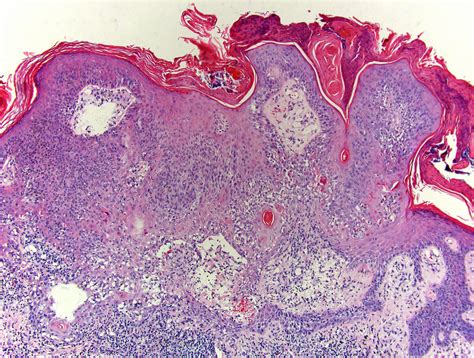

Inflamed Seborrheic Keratosis

To understand the inflamed variant, we must first define the base condition. A seborrheic keratosis is a benign growth that originates from the keratinocytes, which are cells in the outer layer of the skin. They often look like they have been "stuck on" the skin with a waxy or scaly texture. An Inflamed Seborrheic Keratosis occurs when one of these established growths becomes traumatized or irritated. This irritation triggers the body’s inflammatory response, leading to changes in the lesion's appearance and sensation.

• inflamed seborrheic keratosis histology